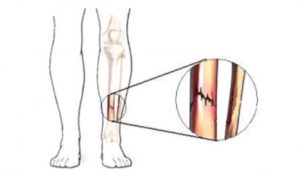

Son fracturas que ocurren generalmente en los pies, producen dolor crónico localizado en un punto, alivian en reposo, aumenta el dolor al caminar o apoyar la zona afectada.

Las fracturas por estrés pueden ocurrir en huesos sometidos a presión constante y repetida, por sobreuso, o micro traumatismos repetidos. Pueden ocurrir en los pies, la rodilla, tibia, peroné, cuello femoral, vértebras, antebrazos etc.